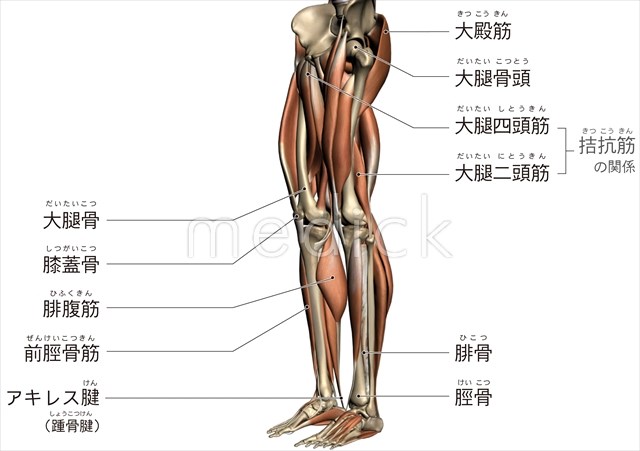

下半身のアタリを描く まずはアタリを描きます。 女性の場合、腰の一番広いところは股と同じ高さにあります。(転子とかいう名前だった気がします) そこで、腰の広い部分を左右に三角形を足して表現しましょう。. 脚のイラスト。 構造を意識した描き方 イラストbyきいも 脚の筋肉はこのようについています。 イラレポへ _2 イラストbyきいも 脚の骨は垂直でなく斜めになっているため、出っ張り方が内側と外側で異なります。骨盤から下の動きに関与する下肢帯の筋肉図鑑。 骨・筋肉・関節可動域など手. 下半身の鍛え方 下半身の鍛え方完全版 大腿の筋肉:大腿二頭筋 膝関節を屈曲させる作用 読みかた:はむすとりんぐす 英語名称:hamstrings 部位詳細: 大腿二頭筋長頭 | 大腿二頭筋短頭 | 半膜様筋 | 半腱様筋.

骨下半身のイラスト 医療のイラスト 写真 動画 素材販売サイトのメディック Medick

骨下半身のイラスト 医療のイラスト 写真 動画 素材販売サイトのメディック Medick

下肢のおもな骨と筋肉のイラスト 医療のイラスト 写真 動画 素材販売サイトのメディック Medick

骨と筋肉 下半身 イラスト No 無料イラストなら イラストac